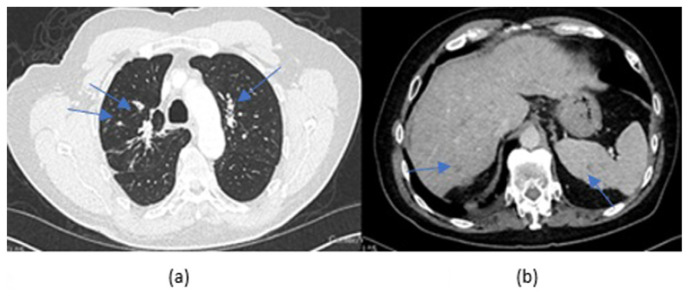

We report a 69-year-old with a past medical history of prostate cancer, and arsenic poisoning, who was incidentally found to have multiple pulmonary nodules and hepatosplenic lesions on CT imaging. He denied respiratory symptoms, but was noted to have significant weight loss. A bronchoscopy revealed mycobacterium kumamotonense on culture. He was treated presumptively for pulmonary and disseminated infection with azithromycin and ethambutol for 16 months, and 12 months of rifabutin after four months of rifampin which was discontinued due to resistance. Patient's weight loss resolved and CT imaging appeared significantly improved.